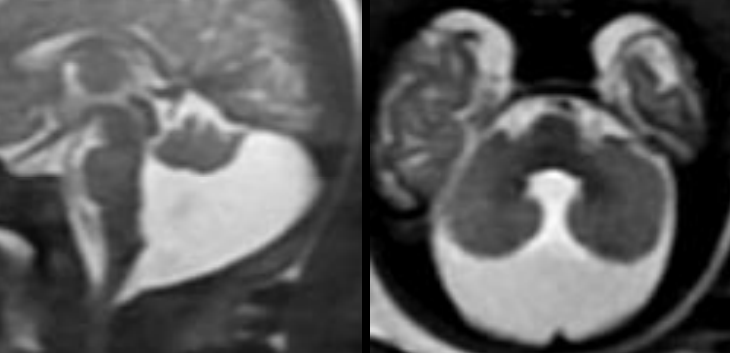

Dandy Walker

Triade

- Hypoplasie du vermis

- Dilatation du V4 (hydrocéphalie sus-tentorielle associée ++)

- Elargissement de la fosse postérieure (ascension du torcular, scalloping occipital)